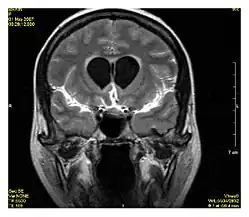

Magnetic resonance angiography (MRA) and venography Time-of-flight TOF Blood entering the imaged area is not yet magnetically saturated, giving it a much higher signal when using short echo time and flow compensation. Detection of aneurysm, stenosis, or dissection[31]

Phase-contrast magnetic resonance imaging PC-MRA Two gradients with equal magnitude, but opposite direction, are used to encode a phase shift, which is proportional to the velocity of spins.[32] Detection of aneurysm, stenosis, or dissection (pictured).[31]

Magnetic resonance angiography (MRA) is a group of techniques based to image blood vessels. Magnetic resonance angiography is used to generate images of arteries (and less commonly veins) in order to evaluate them for stenosis (abnormal narrowing), occlusions, aneurysms (vessel wall dilatations, at risk of rupture) or other abnormalities. MRA is often used to evaluate the arteries of the neck and brain, the thoracic and abdominal aorta, the renal arteries, and the legs (the latter exam is often referred to as a "run-off").